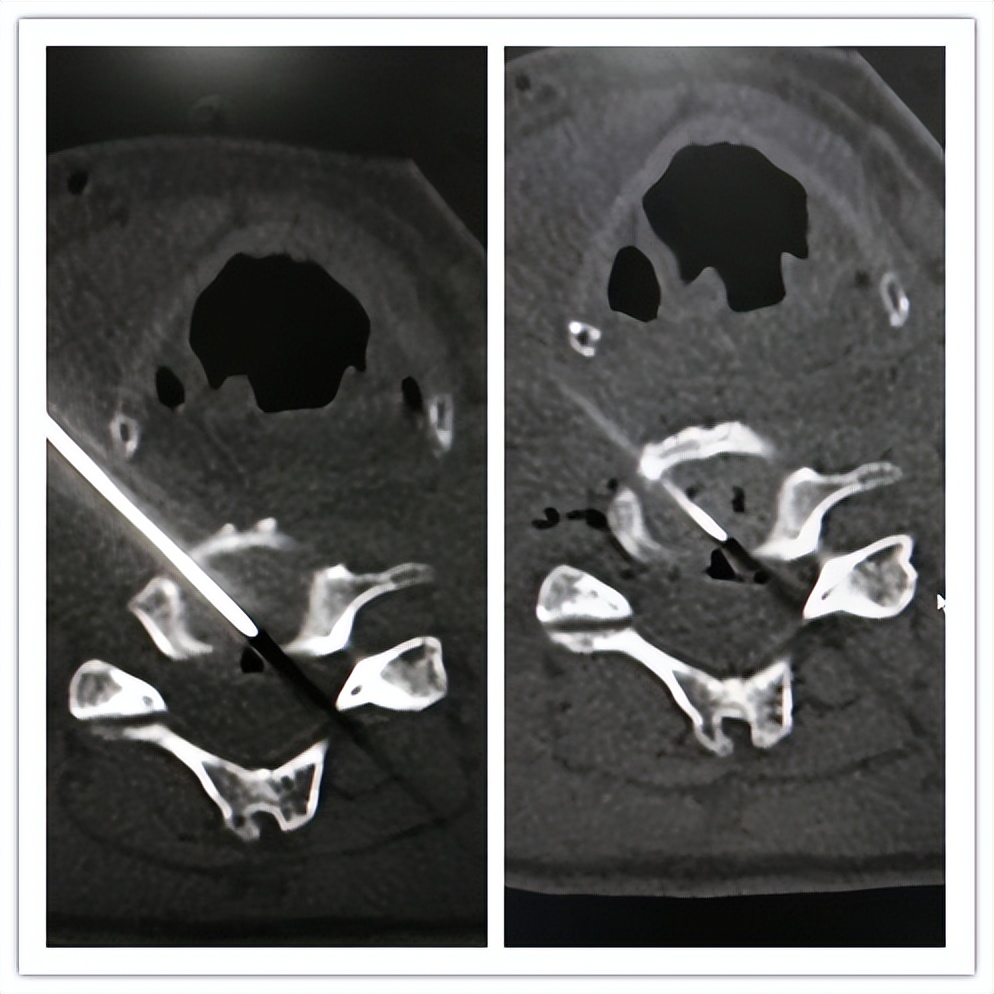

(颈椎间盘突出症:颈椎间盘射频+臭氧消融)

(颈椎间盘突出症:颈椎间盘等离子)

(颈椎间盘突出症:颈椎内镜下颈椎间盘髓核摘除)